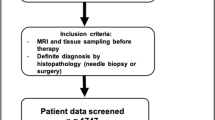

A dataset of 402 malignant and 257 benign lesions was identified. Two radiologists assigned the KS. If a lesion with KS > 4 had ADC > 1.4 × 10−3 mm2/s, the KS was reduced by 4 to become KS+. In order to consider the full spectrum of ADC as a continuous variable, the KS and ADC values were used to train diagnostic models using 5 ML algorithms. The performance was evaluated using the ROC analysis, compared by the DeLong test. The sensitivity, specificity, and accuracy achieved using the threshold of KS > 4, KS+ > 4, and ADC ≤ 1.4 × 10−3 mm2/s were obtained and compared by the McNemar test.